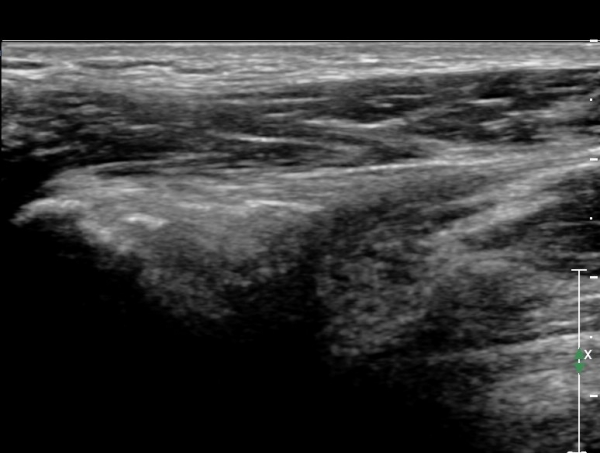

°í°üÀý ¿ÜÃø, ¹Ù·Î µÚ Á¾´Ü¸é°Ë»ç¿Í Ⱦ´Ü¸é °Ë»ç»ó °üÀý ¿Í¼øºÎÀ§¿¡ Ä¿´Ù¶õ °í¿¡ÄÚ ¼®È¸È­°¡ °üÂûµÊ(»çÁø 8, 9)